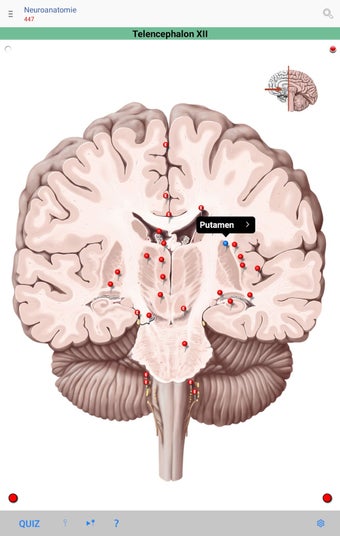

The app consists of different sections, each of which contains information about a specific part of the body. You will learn about the different organs, as well as the muscles, bones, and other important structures. You can test yourself with a unique quiz that consists of multiple-choice questions.